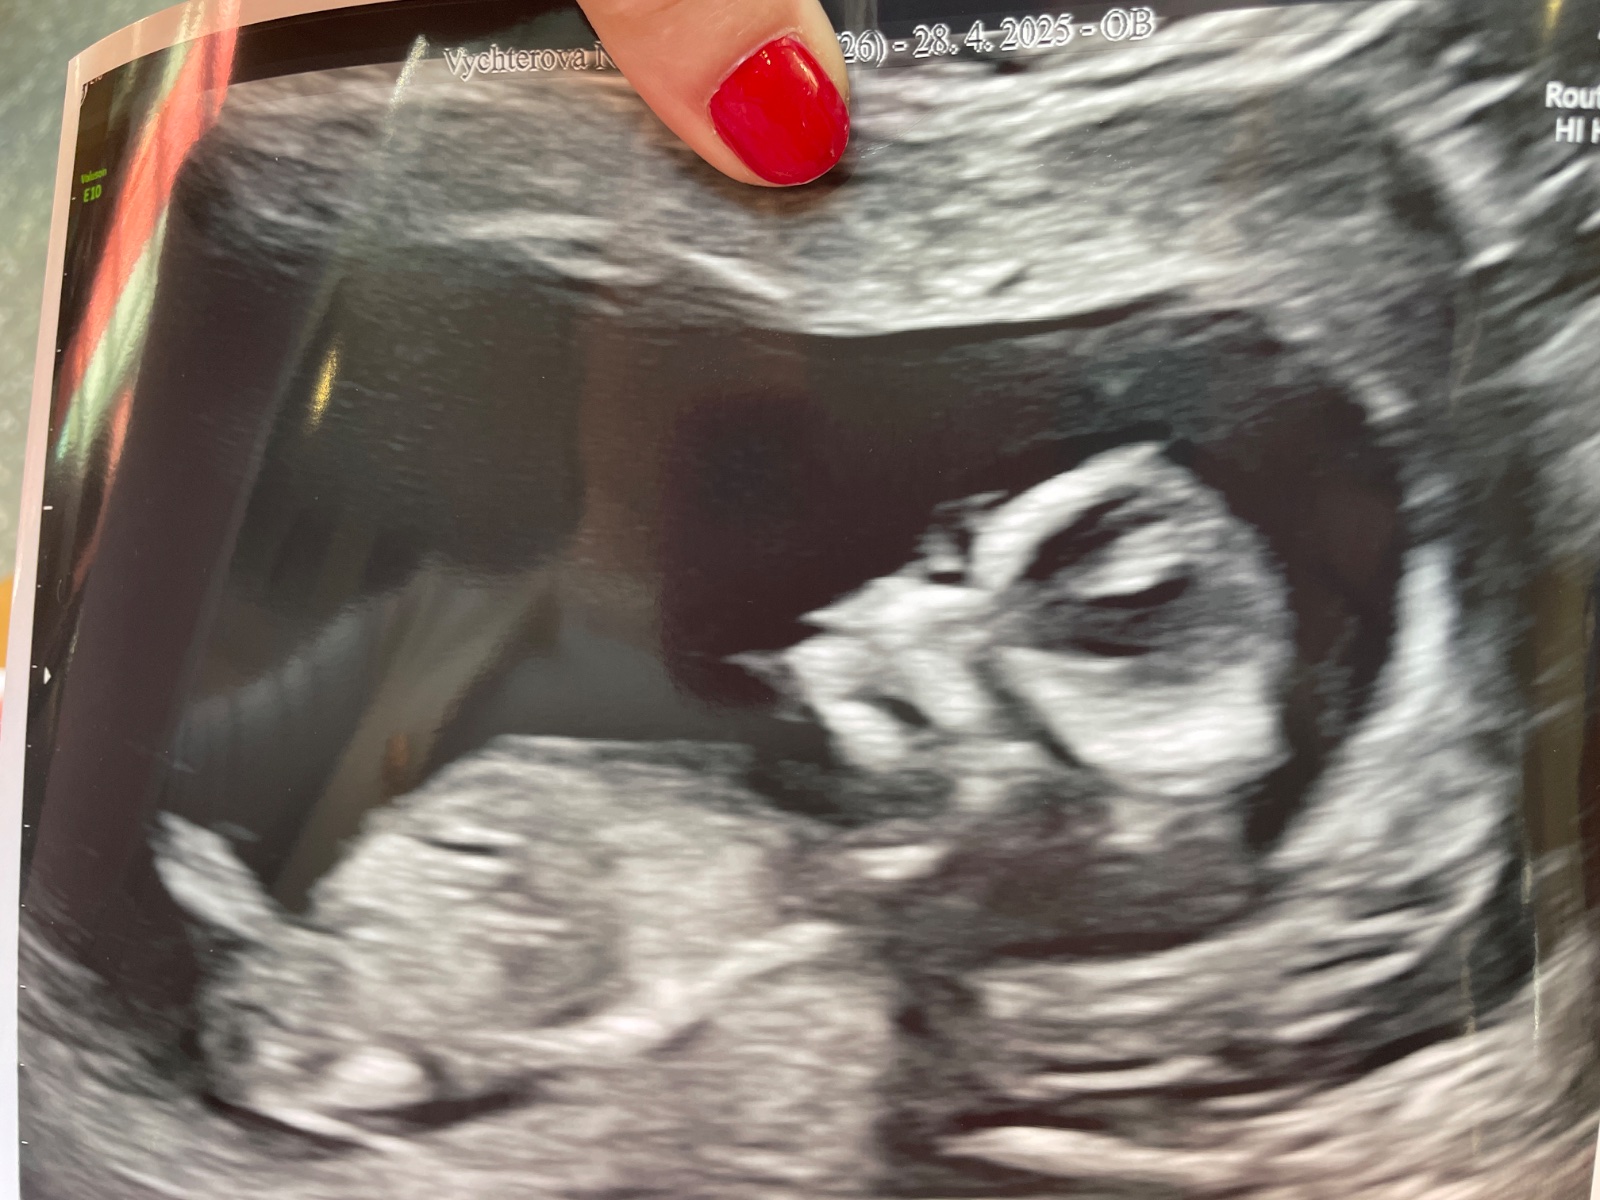

Pohlaví podle ultrazvukového obrázku. Co myslíte?

Ahojky holky , chtěla jsem se prosím zeptat , dnes jsem byla na prvním ultrazvuku na gennetu , jelikož miminko stále leželo na bříšku , tak udělala fotku v rychlosti když se otočilo a říkala že pohlaví není vidět kvůli poloze. I přesto , máte nějaký odhad podle obrázku ? Děkuji a přeji všem krásný den a hodně zdraví 🌞

Tam opravdu není nic vidět. Je to proste 50:50 a čekat na další UZ. Jako podle pupečníkem mi prijde, ze neco trčí nahoru, takže je to kluk, ale to spíš hádám 🤷🏼♀️

"Něco vidět" je obvykle až kolem 16 tt. Do té doby pohlavní orgány vypadají prakticky stejně u obou pohlaví, minimálně pokud je nemáte opravdu hodně dobře nakoukané a pečlivě zabrané přímo ty.

Obávám se, že to, co tak příhodně trčí v oblasti mezi nožičkama, je pupeční šňůra (je vidět linie jdoucí rovně velmi daleko přes tělíčko) a partie, podle kterých se obvykle pohlaví určuje, jsou tím pádem vlastně mimo záběr.